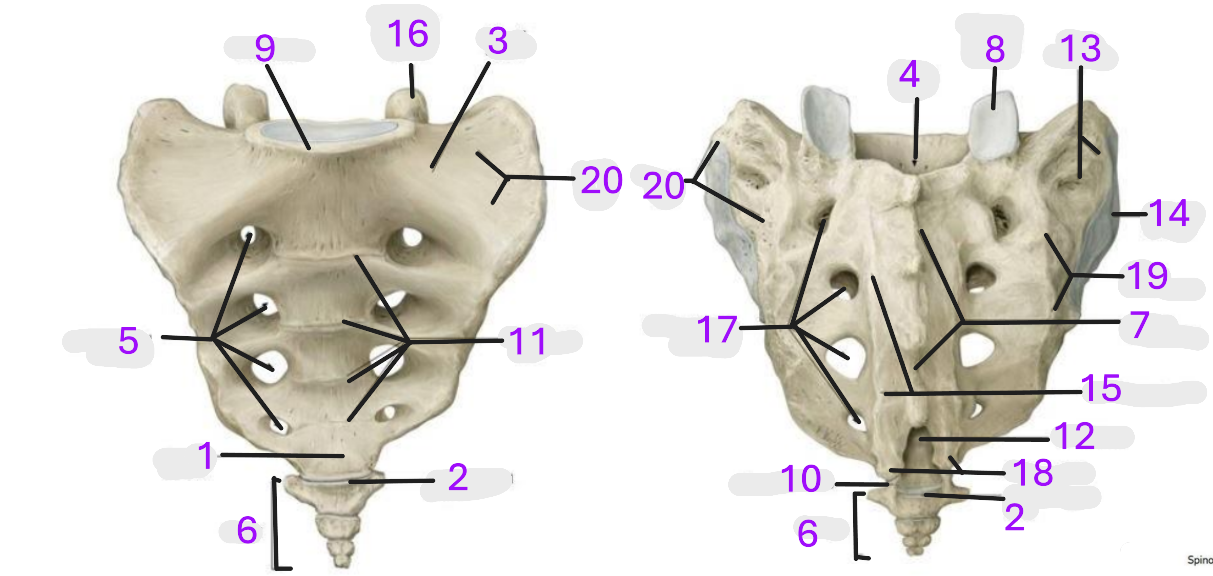

Where is the apex of sacrum

1

Where is the sacrococcygeal joint

2

Where is the wing of sacrum

3

Where is the sacral canal

4

Where is the anterior sacral foramina

5

Where is the coccyx

6

Where is the median sacral crest

7

Where is the superior articular facet

8

Where is the promontory

9

Where is the coccygeal cornu

10

Where is the transverse lines

11

Where is the sacral hiatus

12

Where is the sacral tuberosity

13

Where is the auricular surface

14

Where is the medial sacral crest

15

Where is the superior articular process

16

Where is the posterior sacral foramina

17

Where is the sacral cornua

18